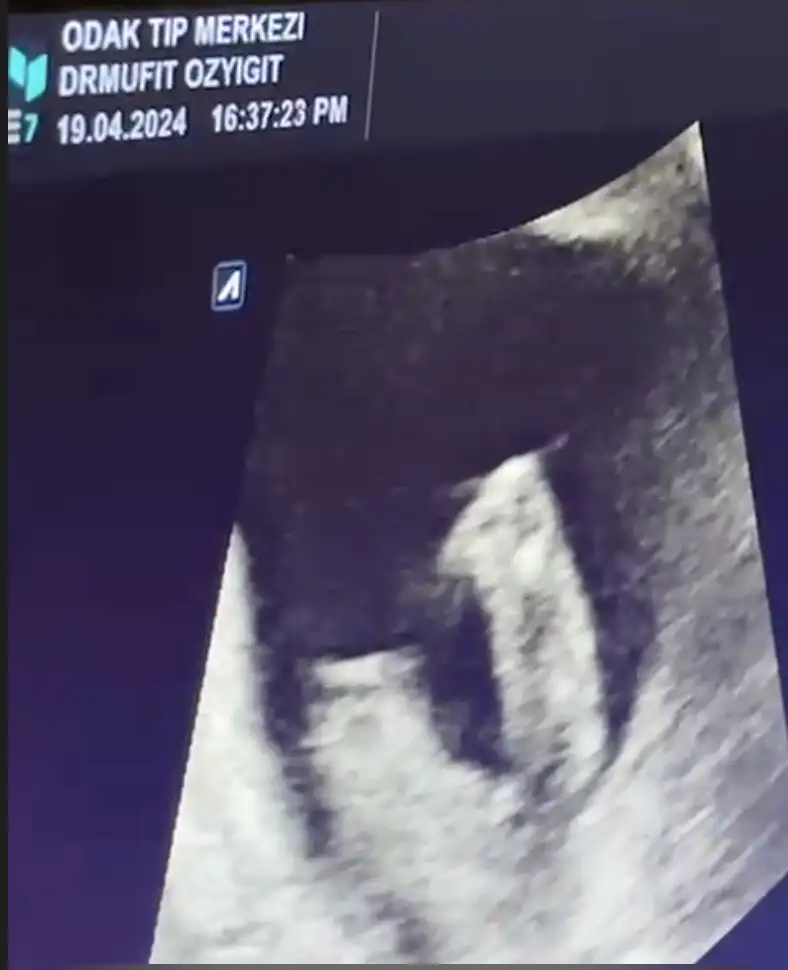

son görüntümüzden minik popomuzu da ekleyelim. 15 haftalığız ölçümlere göre. ama hala kız olduğuna %100 inanamıyorum çünkü iki hafta önce gördüğüm şey resmen pipiydi :KK70: